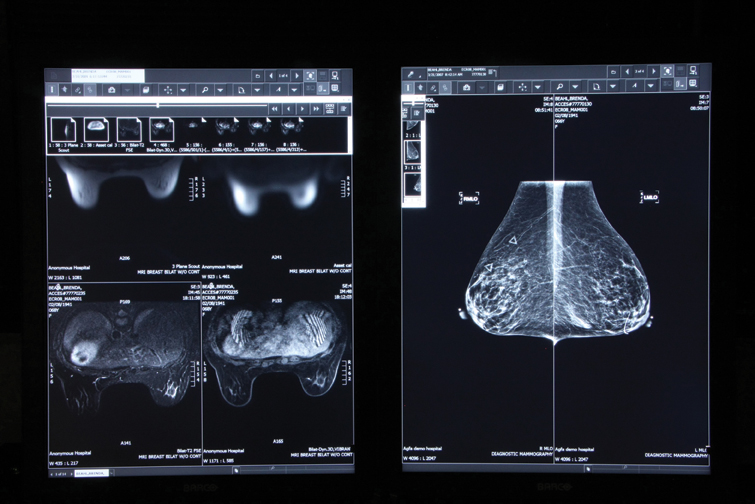

Dense breast tissues make mammograms (right) difficult to read, which may require complementary testing, such as MRI (left). Efforts by state legislatures mandating that physicians inform patients of the challenges of dense breast imaging raise both opportunity and risk for readiologists.

While the federal government has been content to influence the practice of medicine through financial dictates, individual state governments lately have taken a more direct approach. Five states now mandate physicians to inform women with dense breasts that mammography may be of limited value for them. Connecticut, Virginia, Texas, California and New York require physicians to advise patients that complementary imaging studies, such as ultrasound or MRI, may be needed if dense fibroglandular tissues are likely to obscure the mammographic signs of cancer.

Third-party payers in the first states to adopt such mandated education have typically reimbursed for the ultrasound procedures that may follow, although its not required by law. And while ultrasound coverage may be provided, it is seldom there for the MRI exams that might be indicated for women with dense breasts at high risk of developing cancer. When reimbursement is not available, the laws do not address who should shoulder the costs.

Then there are fundamental problems with ultrasound and MRI. Their high sensitivity and lack of specificity lead inevitably to more biopsies and a preponderance of negative findings for procedures that otherwise would not have been performed, as illustrated by early experiences in the first state to enact such legislation, Connecticut.[1]